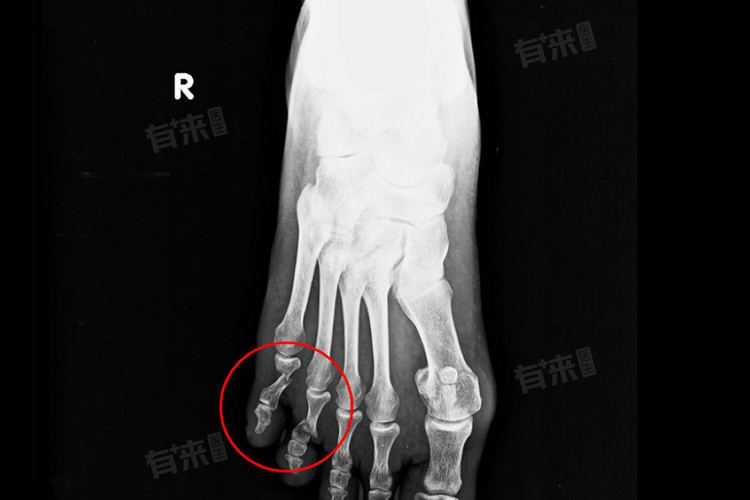

- 初步处理与诊断:脚趾骨折后,应立即停止活动,避免进一步损伤。患者应及时就医,通过X光等影像学检查明确骨折类型及程度,为后续治疗提供依据。

- 手术治疗:若骨折严重,如粉碎性骨折或伴有明显移位,影响正常功能,则需考虑手术治疗。手术包括切开复位内固定,使用钢板、克氏针等材料固定骨折部位,恢复解剖关系,促进骨折愈合。